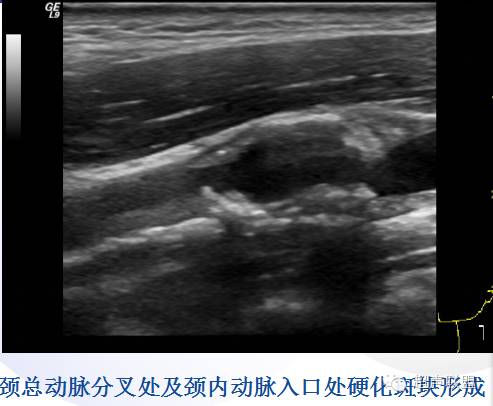

* 病理:本病常见于50岁以上男性,好发于血管分叉处,如颈总动脉分叉处和主动脉弓的分支部位。

主要病理变化:动脉内膜类脂质沉积,逐渐出现内膜增厚、钙化、粥样硬化斑块以及血栓形成,致使管腔狭窄甚至闭塞。

(1)颈动脉壁外膜清晰,内-中膜增厚:内-中膜厚度IMT>0.9mm为早期动脉硬化表现,由类脂质沉积于内膜所致。

(2)颈动脉管壁粥样硬化斑块形成与管腔狭窄: